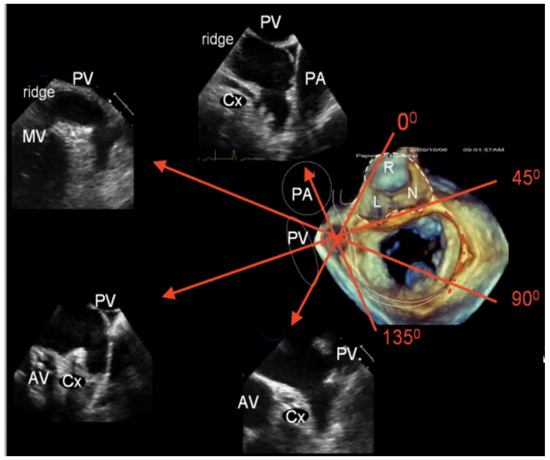

2.2.2. LAA Measurements (Anatomy and Morphology)

2.2.3. Intra-Procedural TOE